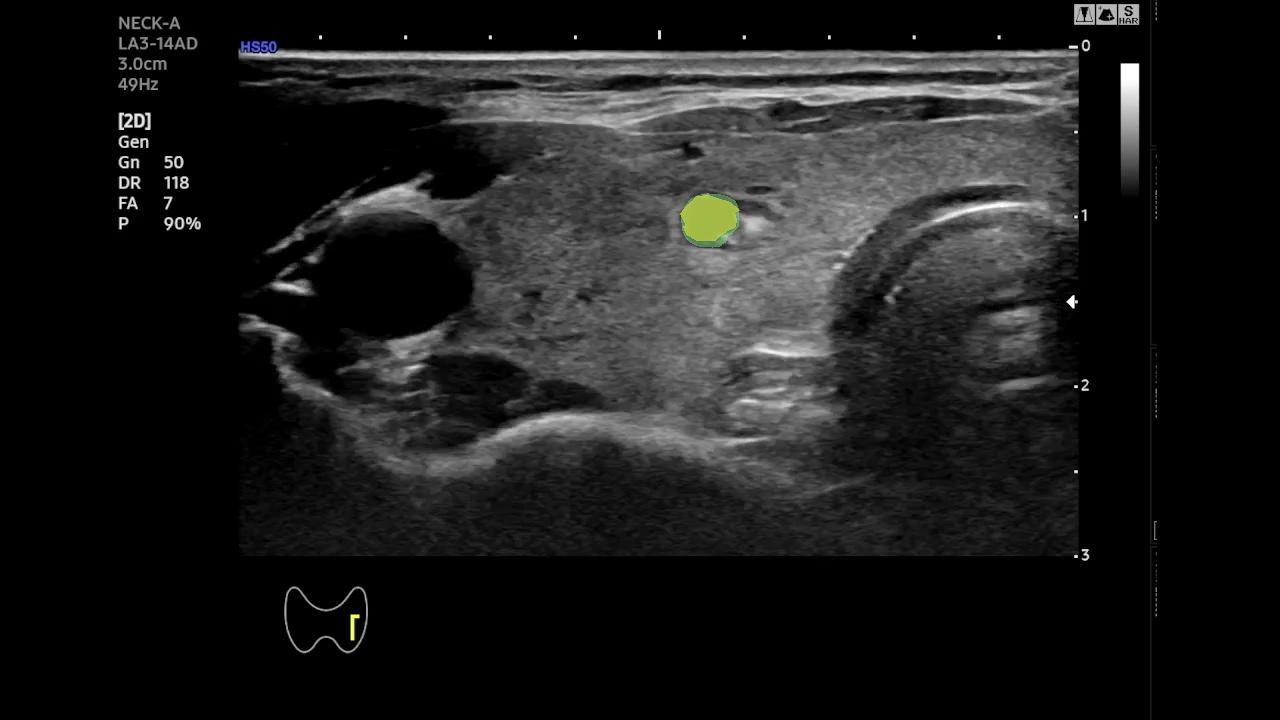

Qualitative Analysis of Temporal Stability- To better highlight the temporal behavior of SAM-2 and EMA-SAM, we visualize predictions at representative frames sampled from a complete RFA sequence. Figure 2 shows a three-row comparison: the first row displays the original ultrasound frames at selected timestamps (with ellipses indicating omitted intermediate frames), the second row shows SAM-2 predictions, and the third row presents EMA-SAM results. As the sequence progresses, SAM-2 occasionally loses the PTMC region when it becomes indistinct or is occluded by RFA bubbles, sometimes mis-segmenting nearby tissue. In contrast, EMA-SAM maintains a coherent segmentation trajectory throughout the sequence. Its confidence-weighted exponential-moving-average pointer preserves a robust latent prototype of the lesion, allowing rapid re-identification and boundary recovery once the PTMC reappears.

Original

SAM2

EMA-SAM